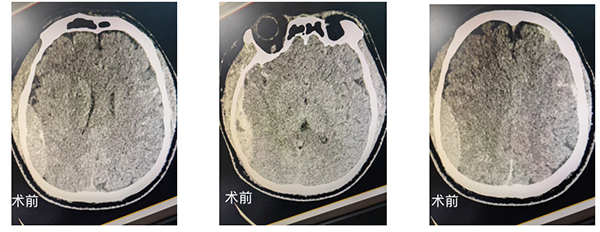

急诊医护团队第一时间开展清创缝合,但患者随即出现神志昏迷、一侧瞳孔散大,左:右约为直径2mm:5mm,对光反射消失,伴随尿失禁、频繁呕吐等症状,呕吐物带有浓烈酒臭味。神经外科值班医生张腾飞接到急会诊通知后,火速赶到现场,并向神经外科执行主任胡业帅汇报,胡主任和李志东医生也连夜驱车驰援。CT检查结果印证了最坏的预判:患者存在右侧颞顶硬膜外血肿、左侧半球弥漫性出血及骨折,颅内压力持续升高,随时可能因脑疝危及生命。

更棘手的是,家属迟迟无法联系。神经外科胡主任当机立断“生命至上!立即请示医院总值班开通绿色通道,马上手术!”。医院按照急诊救治规范启动应急预案。急诊争分夺秒做好术前准备,直接将患者送进手术室。术中,胡主任带领张腾飞、李志东两位医生精准操作,于复杂的颅内结构中清除血肿、止血减压,麻醉科与护理团队密切配合,全程守护患者生命安全。